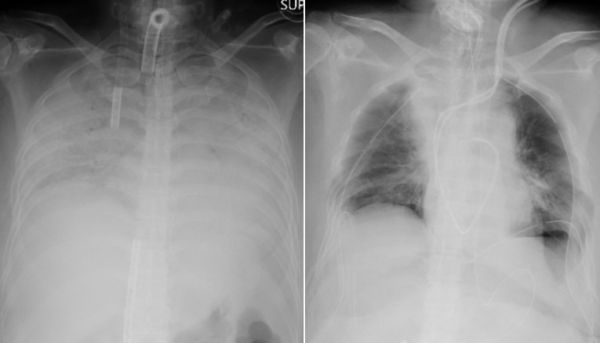

Η πορεία της πανδημίας του κοροναϊού αναπτύσσεται με ταχύ ρυθμό, εκθετικά, με αύξηση 9% των κρουσμάτων την περασμένη εβδομάδα, έβδομη συνεχόμενη εβδομάδα αυξητικής τάσης και με 5% αύξηση των θανάτων